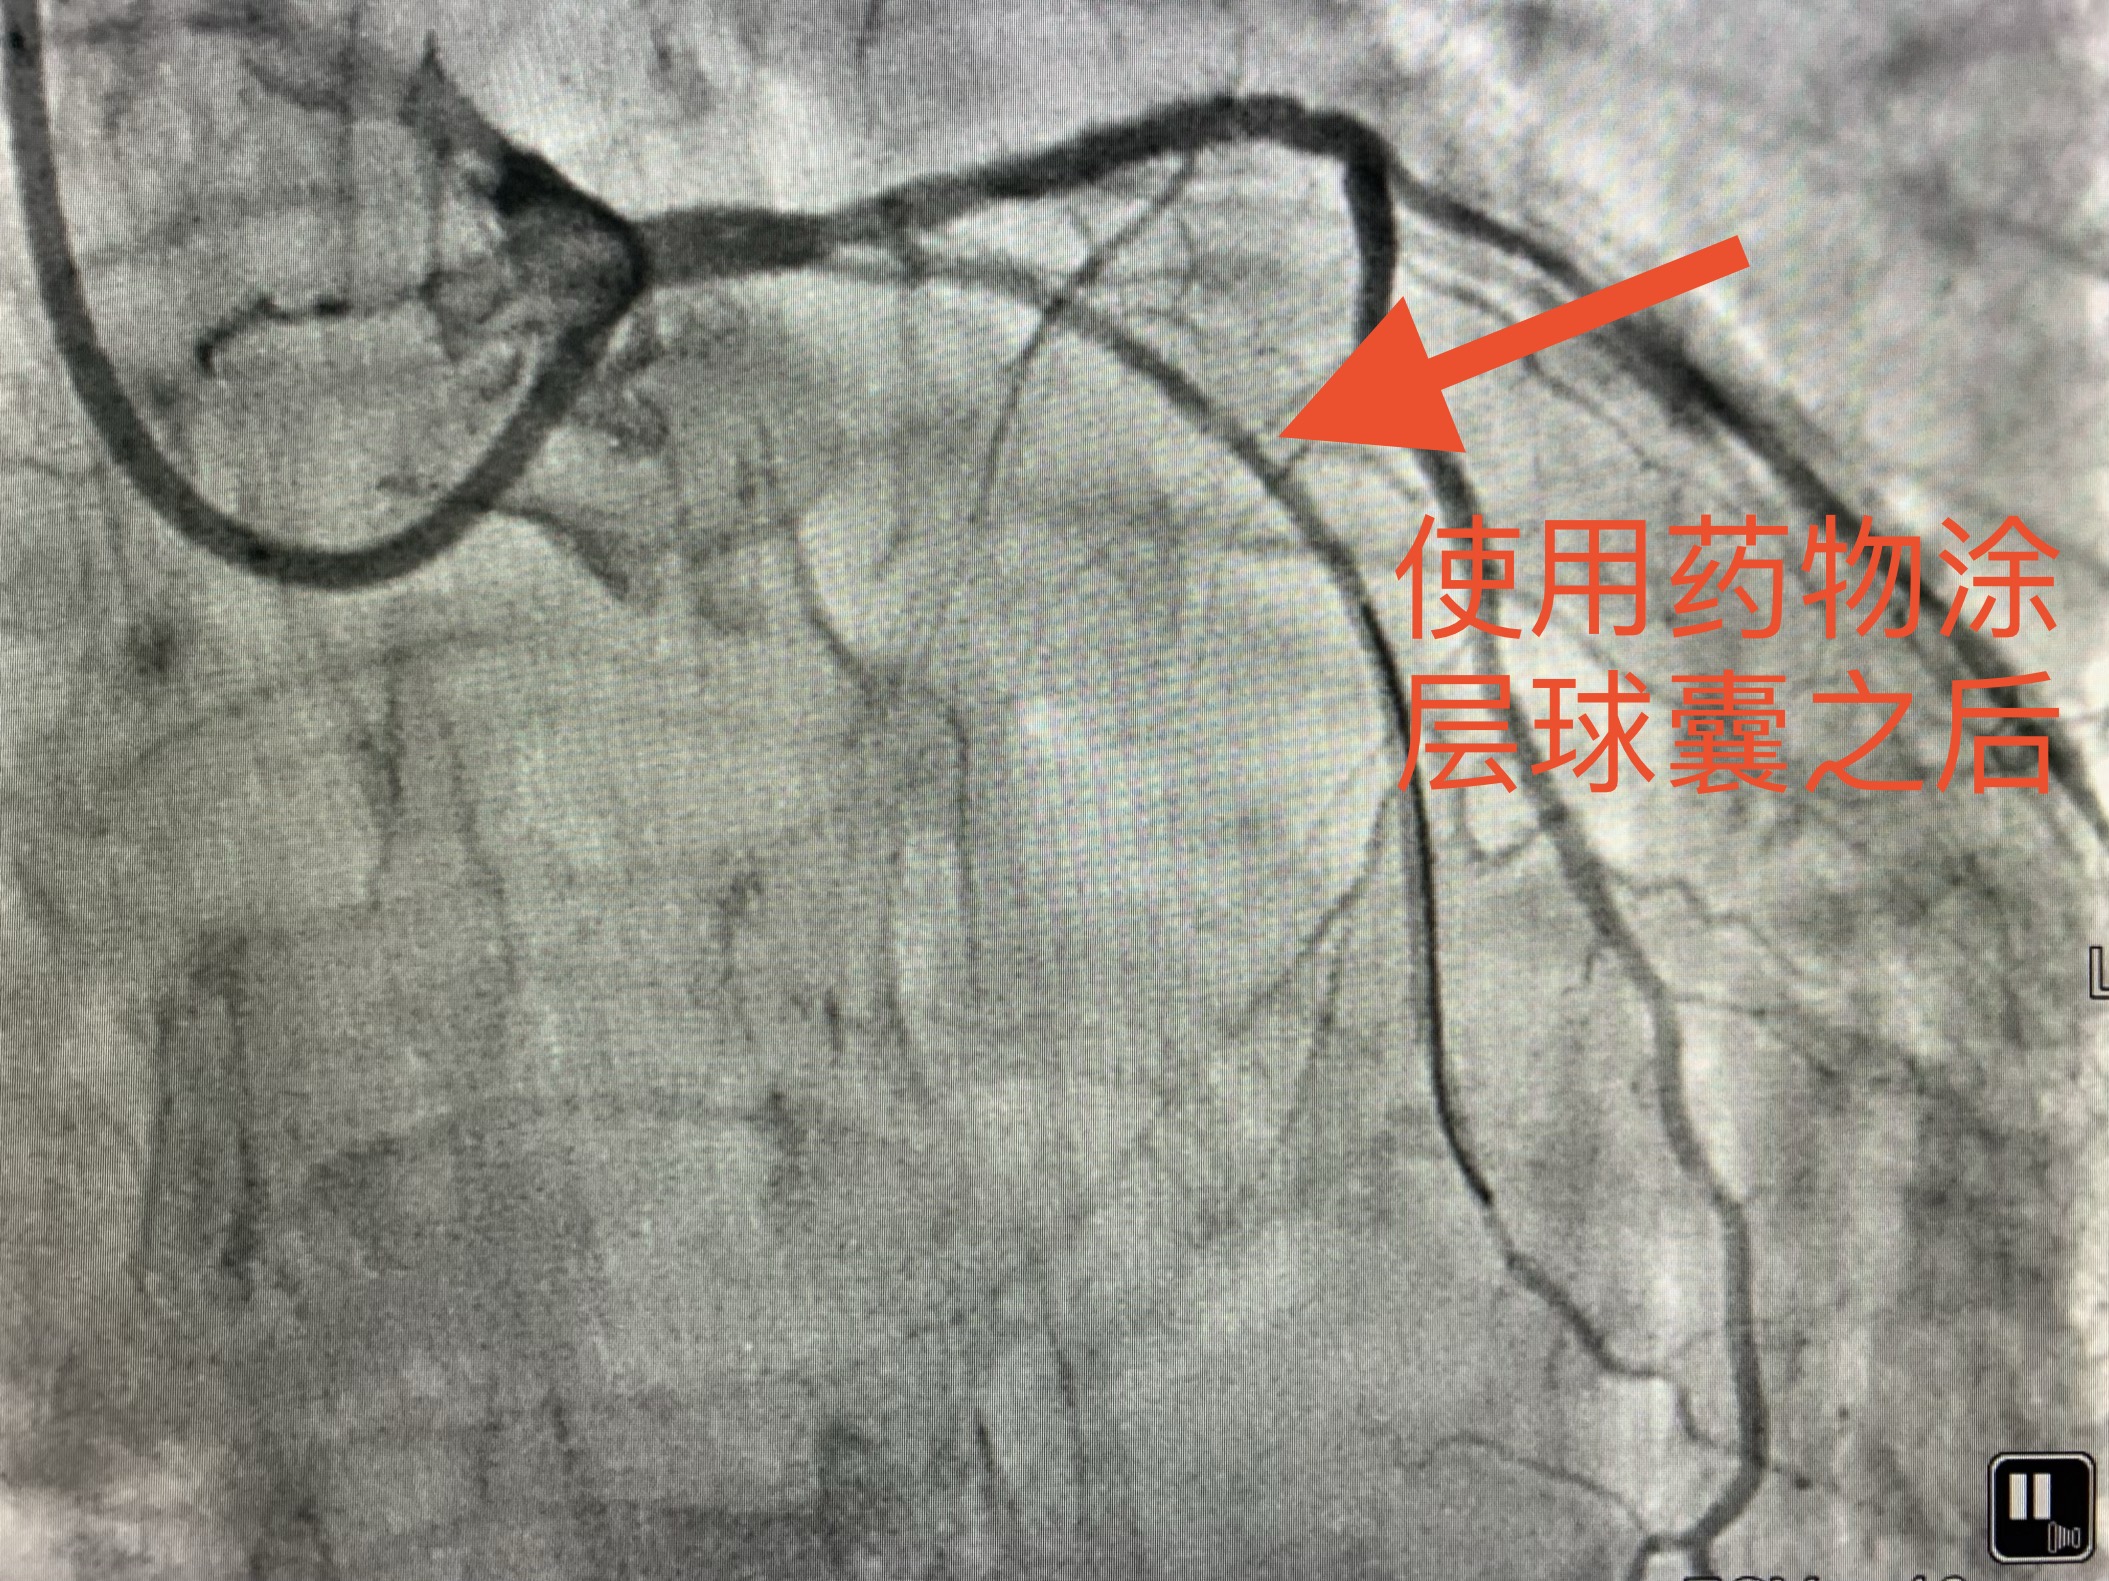

术后老赵身体恢复的很快,再也没有出现胸闷、胸痛的症状。老赵对治疗效果感到非常满意。(使用药物涂层球囊介入处理后的效果见下图)

心血管介入团队通过约2毫米的微小创口,经冠状动脉将药物涂层球囊送到狭窄病变处,球囊上载有防止血栓和血管狭窄的药物,到达病变位置后,扩张球囊,药物便贴粘至病变部位,随后撤出球囊和导管,使此处病变血管节段恢复达到有效管腔面积和正常血流,并减少再狭窄的几率即达到治疗目的。患者体内未植入任何器械。